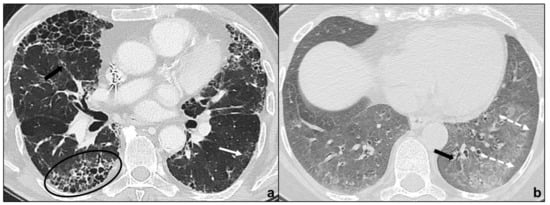

Cryptogenic Organizing Pneumonia